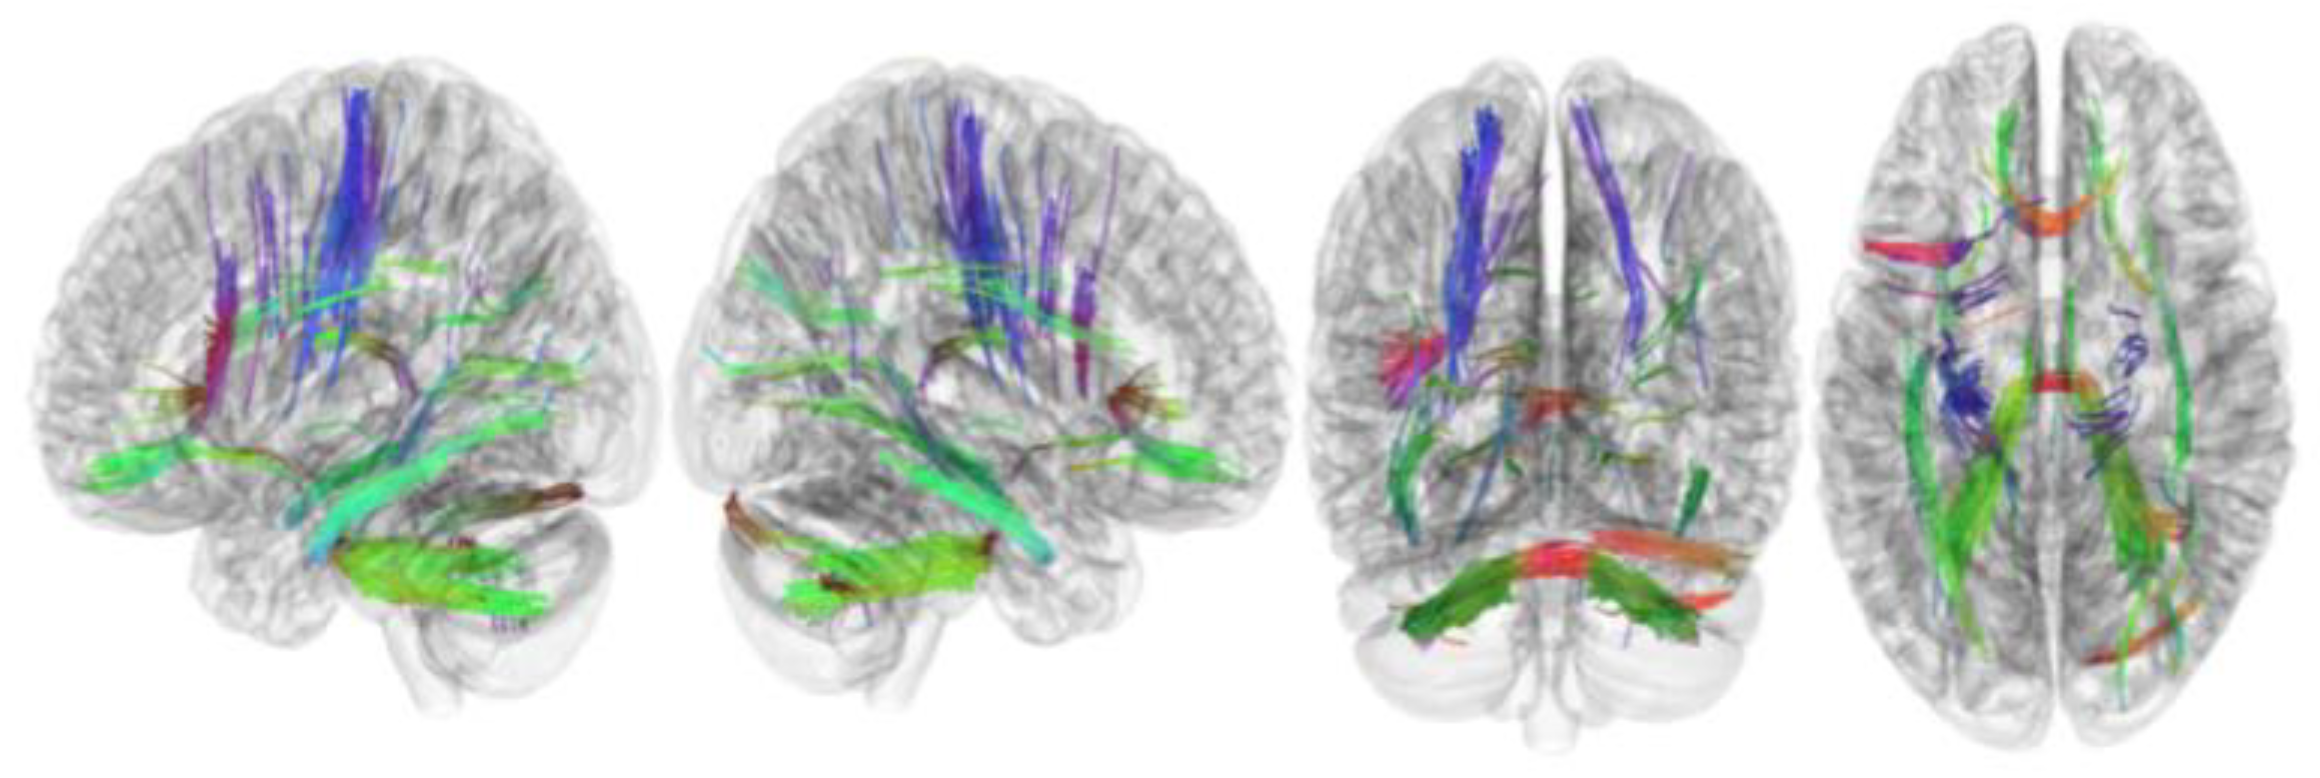

3.3. Tracks with QA Correlated with RLS Severity

| QA | |

| Tracks with positive or negative correlation with RLS severity | None |